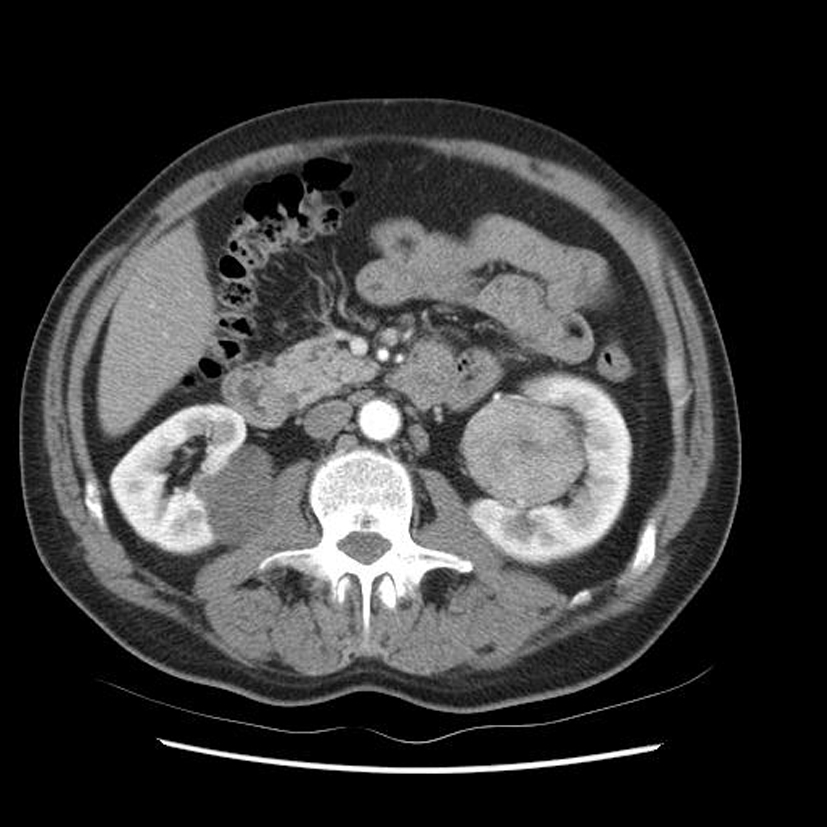

Diagnostic?

Petite tumeur rénale droite trouvée de manière fortuite sur un scanner